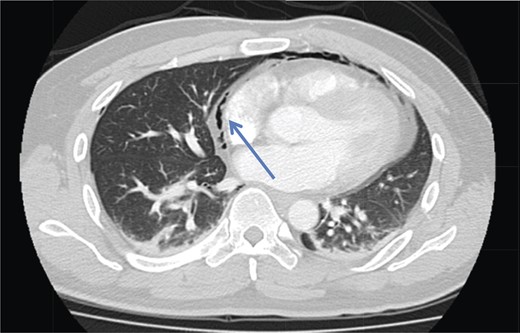

A 42-year-old male with a past medical history of hypertension was admitted for an elective TEP repair of his left inguinal hernia. Endotracheal intubation and general anesthesia were given uneventfully. The extraperitoneal space was developed with a balloon space maker, and insufflation of carbon dioxide at a maximum pressure of 12 mmHg was performed. Intraoperatively, a large incarcerated indirect left inguinal hernia containing omentum was reduced. A Optilene mesh (10 × 12 cm) was placed and tacked appropriately after hernia reduction. There were no obvious tears in the peritoneum and the total operative time was ∼90 min. No elevation of end-tidal CO2 was noted during the surgery and the patient was extubated successfully. The patient subsequently complained of left-sided chest pain on the same night of the surgery. He did not have abdominal pain. He had subcutaneous crepitus extending from the left groin to the left chest. His cardiac enzymes were negative and his electrocardiography revealed a sinus rhythm with no acute ischemic changes. A plain radiograph of the chest showed a sliver of lucency in the mediastinum suspicious for pneumomediastinum, with no obvious pneumoperitoneum or pneumothorax seen (Fig. 1). Computed tomographic (CT) imaging of the thorax and abdomen confirmed the radiograph finding of pneumomediastinum and diffuse subcutaneous emphysema tracking along the abdominal muscles bilaterally, as well as a small amount of free air and stranding in the left posterior pararenal space (Figs 2–4). The patient was treated conservatively with oral analgesia and supplemental oxygen. His chest pain resolved by the third postoperative day and he was discharged well. He was advised to avoid air travel for 1 month. He was reviewed in clinic at the 1-week and 1-month intervals and did not report any further chest pain or respiratory symptoms. His operation site healed well and he remained recurrence free.

Axial section CT pulmonary angiogram shows a pneumomediastinum (arrowhead).